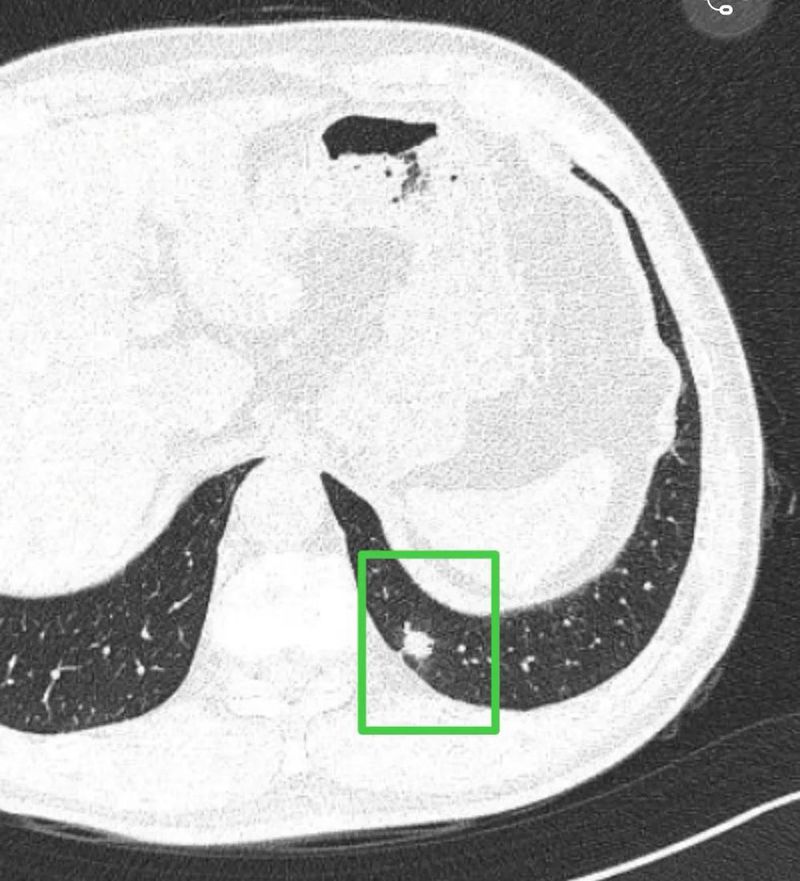

患者,男性,61岁。患者于2025年6月1日CT检查偶然发现双肺结节,最大12mm。患者自述无不适症状。

右侧未见明显有意义的结节。左肺下叶多发结节,黄色的结节微小,绿色的相对较大。主病灶轮廓显模糊,实训部分的外围有晕征,这种实性密度伴有周围晕征的容易是感染性病变。如果主病灶是感染性,那么另外小点的两处也有可能是同样致病因素导致的感染性病变。加上又是首次发现,建议先口服消炎治疗10~12天,三个月左右复查一下看看有没有吸收好转。我觉得大概率就是炎症性。当然如果到时候没有显著的吸收,那样的话要查一查结核与隐球菌方面,当然也可以近期在口服消炎治疗的同时查隐球菌与结核。如果隐球菌阳性,那就要抗真菌治疗。意见供参考!